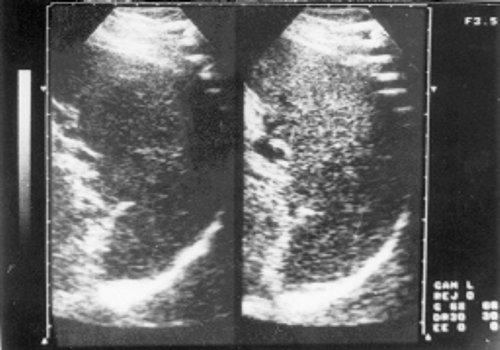

При УЗИ у всех больных 1 группы хроническим лимфолейкозом выявлено увеличение правой доли печени и у 70% - левой. Нормальные размеры селезенки определялись только в 13% случаев. У 66,6% больных в брюшной полости обнаруживаются увеличенные лимфатические узлы. Однако угол наклона левой доли печени мало отличался от физиологического и составлял 45-50º. В то же время при прогрессировании лимфопролиферативного процесса наблюдалось утолщение левой доли и расширение ее угла наклона, который у больных 2 группы достигал 60-70º. При этом отмечалось и более отчетливое увеличение размера правой доли с закруглением ее краев. Анализ гепатограмм показал, что у больных 1 группы эхогенность органа снижалась, иногда обнаруживались участки, резко обедненные эхоструктурами, а звукопроводимость их возрастала (рис. 1). При прогрессировании болезни одновременно с ростом печени, заметно усиливалась ее эхогенность (рис. 2). В паренхиме печени выявлялось большое количество звуковых сигналов крупного и среднего размера, что объясняется разрастаниями в печени соединительной ткани и ее фиброзированием. Отмечалось повышение уровня сигналов от стенок сосудов и портальных трактов. Количество сосудов уменьшалось, особенно у пациентов, страдающих хроническим лимфолейкозом более 5-6 лет, вены плохо наполнялись кровью и нередко были смещены и разветвлялись под тупым углом.

Рис. 1. Эхограмма печени больной хроническим лимфолейкозом (стадия А).

1 - левая доля печени; 2 - правая доля печени.